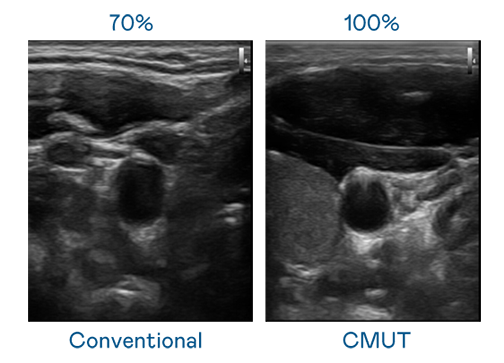

CMUT 技術是一種用電容式微機電元件來產生超音波訊號的技術。與傳統 PZT 壓電式技術相比,CMUT 頻寬增加 30%,更寬頻的超音波訊號讓影像解析度大幅提升,是實現高影像品質醫療超音波掃描、促進精準醫療發展的關鍵技術。

大頻寬帶來超清晰影像

超音波影像的解析度高低,首先取決於探頭能發出的訊號頻寬。DG视讯 CMUT 可提供高清晰的超音波訊號,提供高頻寬、高靈敏度、影像紋理細節更高的超音波影像,協助醫護人員縮短影像判讀時間及利用精準的醫療影像進行診斷。